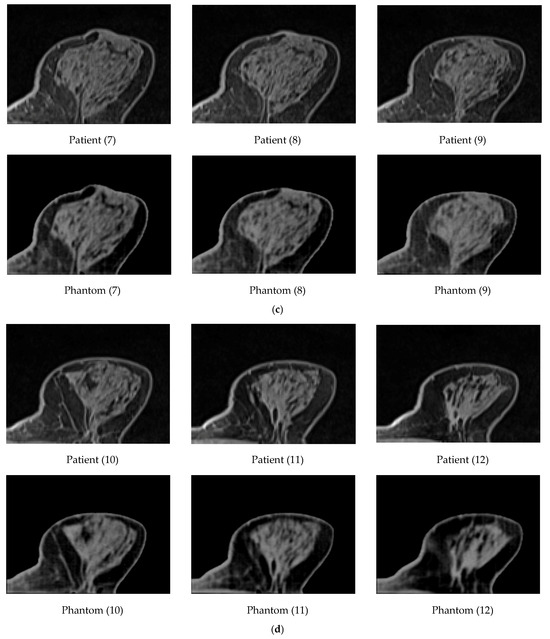

A GE Lightspeed 4-slice CT simulator was used for the CT scanning of the produced phantom. Twelve (12) original images of the patient and twelve (12) from the phantom were selected for comparison, as shown in Figure 9. Specifically, this figure presents representative axial slices from patient data and the corresponding 3D breast phantom. Each slice contains realistic distributions of glandular and fatty tissues. At the level of the original images, no visually striking differences are expected, as the phantom is designed to reproduce the anatomical appearance and attenuation properties of real breast tissue. Therefore, the similarity between patient and phantom images demonstrates the anatomical realism of the phantom rather than highlighting distinct visual features.

Figure 9.

Twelve (12) images (first raw in (a–d)) of the patient and twelve (12) images from the phantom (second raw in (a–d)) were selected for comparison.

To optimize visualization, a window width (WW) of 483 and a window level (centre, WL) of 242 were applied to the original patient images. For the phantom data, a WW of 540 and a WL of 95 were selected, respectively. The results led to a high correlation between the patient’s images and the phantom’s images. The breast area was isolated using a threshold technique for both the patient’s and the phantom’s images, as shown in Figure 10. The histogram of each image (Figure 11) was calculated, and showed a similar pattern, demonstrating that the method was sufficiently accurate to produce HUs consistent with those defined by Equation (8) and used for the fabrication of the phantom. It can be observed that the diagram patterns follow the initial calibration process, where a grey value of 50 corresponds to −100 HU (adipose tissue), while a grey value of 255 corresponds to 100 HU (assigned to skin and gland), across all compared images. Finally, four (4) plot profiles were drawn in similar positions, once again demonstrating a pattern consistent with the produced phantom, as shown in Figure 12 and Figure 13.

Generally, it can be noticed that the original patient images are sharper than the phantom images (Figure 9), and, upon closer observation, some minor tissue components may be missing. This can also be seen in Figure 13, where profile plots were drawn at approximately similar positions in both the patient and phantom images. It should be noted that the phantom images were selected manually in an attempt to identify the most representative slices compared to the original patient images; therefore, the images are inherently affected by contributions from the CT slices located above or below the selected slice. The use of a narrower nozzle, or a CT scanner with lower pixel spacing, could potentially improve the sharpness of the phantom images.

Overall, the correspondence between the measured Hounsfield Unit (HU) values and the established calibration model remained satisfactory, indicating stable and reproducible performance of the proposed approach. In addition, the strong visual similarity observed between the original patient images and the corresponding CT scans of the printed phantom further supports the robustness of the method, as illustrated in Figure 9. Both quantitative HU agreement and qualitative image resemblance suggest that the proposed voxel-wise control strategy is capable of reliably reproducing clinically relevant density patterns.